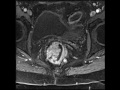

Rectal Cancer

Multiple MR images demonstrate a mass arising along the right aspect of the rectum, with a large polyploid component, as well as extension involving the rectal wall from roughly the 9:00 to 12:00 positions. The mass does appear to demonstrate mesorectal involvement. This is a classic example of rectal cancer with mesorectal involvement.